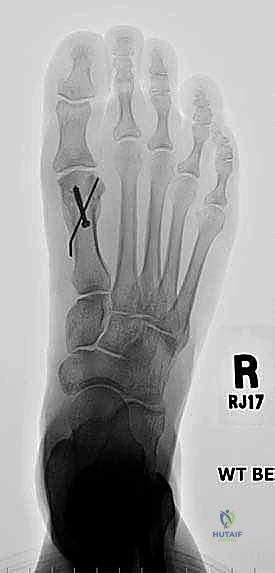

* الأشعة السينية العادية (X-rays) أثناء الوقوف: هذا هو الفحص الأهم. يتم أخذ صور للقدمين أثناء تحمل الوزن لقياس زوايا العظام بدقة، وتحديد مقدار النقص في طول مشط القدم الأول مقارنة بالثاني (يجب أن يكونا متقاربين في الطول ضمن نسب محددة).

الخطوة الثالثة: قص العظم (Osteotomy)

باستخدام منشار جراحي ميكروسكوبي دقيق، يقوم الدكتور هطيف بقص عظم مشط القدم. تعتمد زاوية وشكل القص (مثل القص المائل أو القص على شكل حرف Z) على مقدار الإطالة المطلوبة وشكل العظم المتبقي من الجراحة السابقة.

الخطوة الخامسة: التثبيت الداخلي القوي (Internal Fixation)

لضمان التئام العظم في وضعه الجديد والطويل، يجب تثبيته بقوة شديدة. يستخدم الدكتور هطيف أحدث الشرائح المعدنية التيتانيوم ذات الزاوية الثابتة (Locking Plates) والمسامير الدقيقة. هذا التثبيت القوي يمنع أي حركة بين العظام ويسمح ببدء العلاج الطبيعي في وقت مبكر.